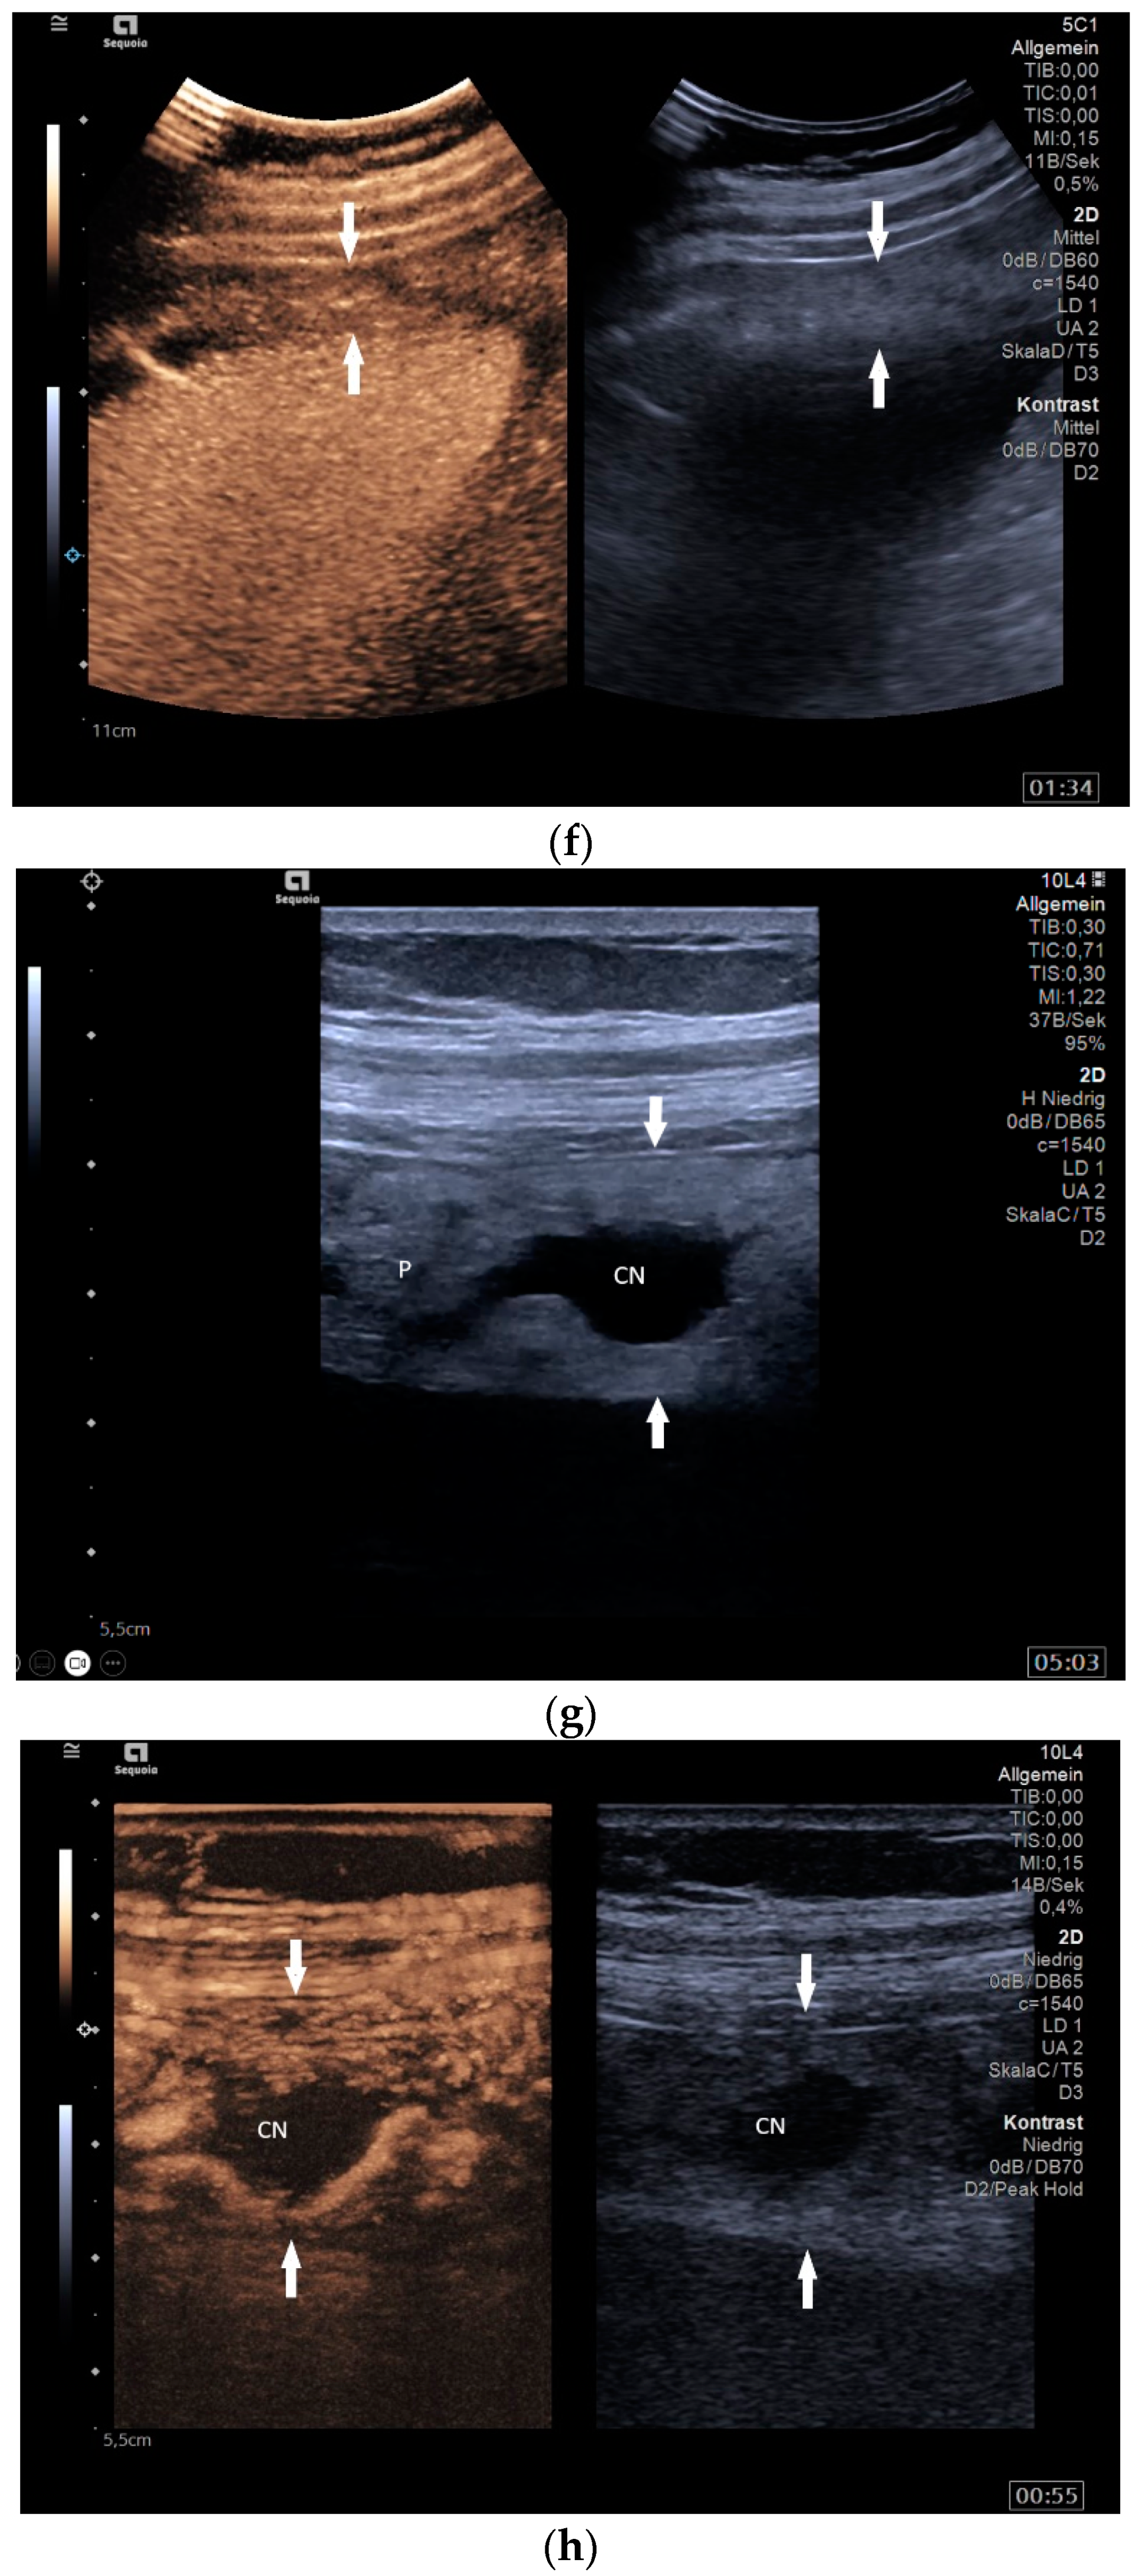

What can be seen sonographically? Ascites can be either diffuse or focal type [Figure 1a,b]. Due to the protein and cell content, these tend to be echogenic, rather than non-echoic. Attention must be paid to enlarged lymph nodes at the same time. Any thickening of the peritoneum and mesentery must be specifically searched for. This also applies to macronodular changes in the peritoneum and mesentery [Figure 1c–h]. The smallest speck-like deposits are usually not visible on ultrasound [36]. With ascites, it may be possible to observe the adhesions [31,37]. Kumar et al. were able to histologically detect granulomatous inflammation in 17/19 (89%) patients using ultrasound-guided needle biopsy of omental thickenings. In a country like India, the authors interpreted this as a manifestation of tuberculosis [32].

Figure 1.

Typical changes in the peritoneum, mesentery, and omentum in patients with tuberculosis. Ascites with pronounced septa (a). Ascites encapsulated between the abdominal wall and colon (b). Omental thickening with non-echoic caseous abscesses and few echogenic contents (c); hypoechoic nodules in hyperechoic thickened peritoneum (d). Significantly thickened hyperechoic peritoneum in B-mode US (right side of image) (marked with arrows). In CEUS, the thickened peritoneum is contrast enhanced in the arterial phase (e). In the parenchymal phase, it shows a decrease in enhancement (f). The thickened hyperechoic peritoneum shows a non-echoic lesion (arrow) (g). In the CEUS, this is not enhanced and instead shows a hyperenhanced rim. This corresponds to caseous necrosis (h).